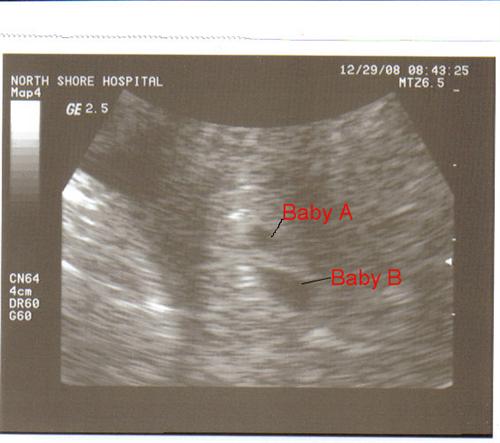

Our Christmas Miracle.....Update 12/29

Update 12/29: 2nd Beta

I went today for our second beta & 5 week ultrasound. My number is now 5319 & we saw 2 sacs!!! Looks like we have twins on our hands!!!!